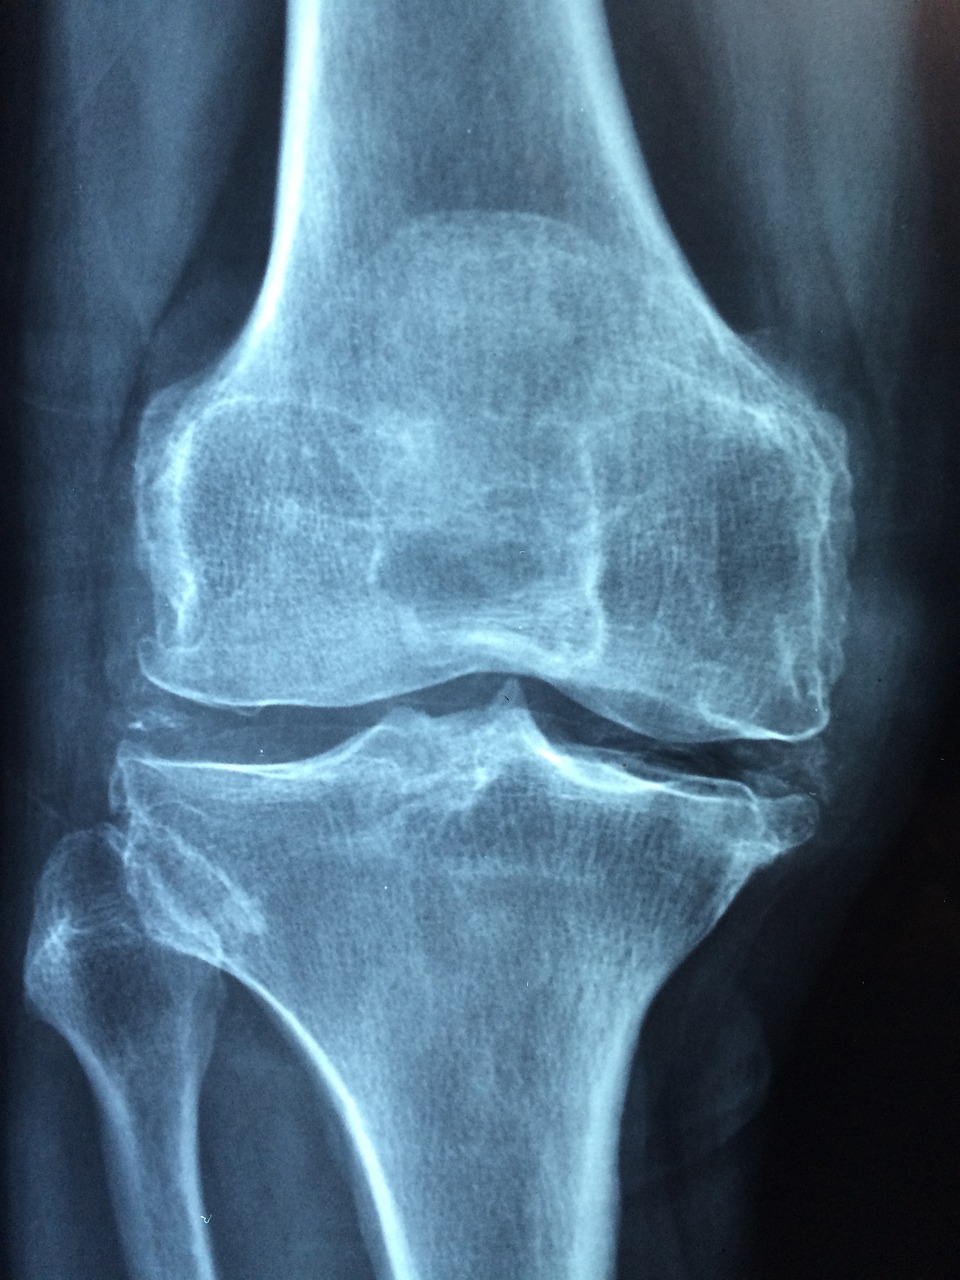

✅ 무릎 인공관절 수술 후 염증은 조기에 발견하면 비교적 간단한 치료로도 회복이 가능하지만,

늦어지면 재수술이나 장기적인 손상으로 이어질 수 있습니다.

다음과 같은 경우에는 꼭 병원 진료가 필요합니다:

● 통증이 일상생활에 지장을 줄 정도로 심할 때

● 부기와 열감이 3일 이상 지속될 때

● 진물이 나오거나 실밥 주변에서 냄새가 날 때

● 열이 나거나, 몸살 증상이 동반될 때

● 수술 부위를 만졌을 때 고름이 느껴질 때

💡 병원에 방문할 때는 증상이 시작된 시점, 진행 정도, 복용한 약 등을 메모해가면 진단에 도움이 됩니다.

👉 가까운 정형외과나 무릎 전문병원에 문의하시고,

수술을 받았던 병원이라면 더욱 정확한 판단이 가능합니다.